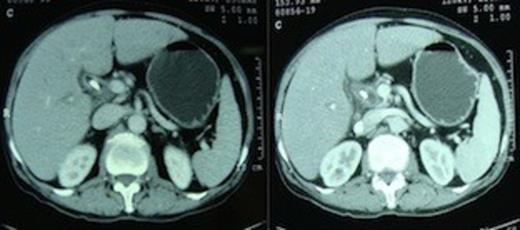

The transverse mesocolon was intact with its anterior layer reflecting onto the lesser sac in the form of a peritoneal reflection covering the anterior aspects of splenic artery and vein. Only the head and uncinate process comprised the entire pancreas, which were normal in size and consistency with no evidence of any compensatory hypertrophy, enlargement or findings suggestive of acute or chronic pancreatitis. Resection was easy, with no need to create a tunnel as there was no pancreas overlying the portal vein and a pylorus preserving pancreaticoduodenectomy was done. Reconstruction comprised only of hepaticojejunostomy and duodenojejunostomy. The cut section of the resected specimen showed only the major papilla with a friable ampullary growth, there was no minor papilla (figure 4).

Pancreaticoduodenectomy specimen with longitudinally cut open medial wall of duodenum and bile duct showing only the major papilla (cannulated with a tube) with ampullary growth, minor papilla is absent.